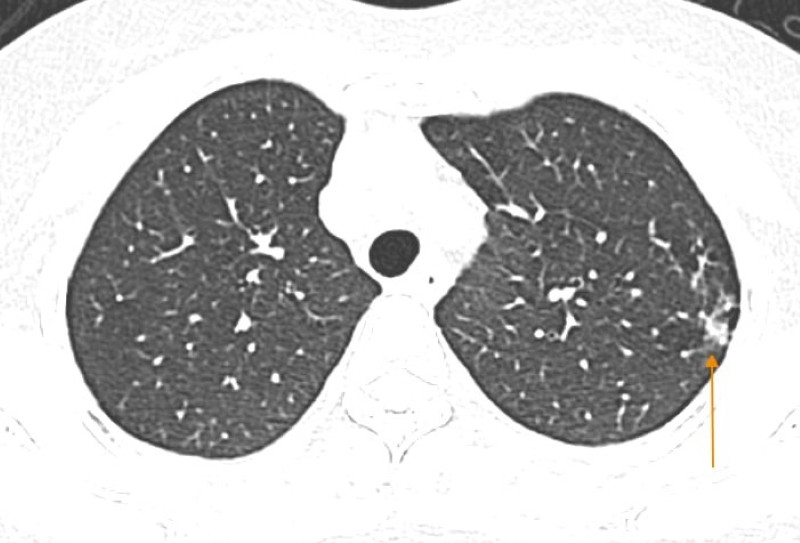

Bác sĩ chỉ định thực hiện các kỹ thuật cận lâm sàng cần thiết phục vụ chẩn đoán. Trong đó, xét nghiệm cúm A cho kết quả dương tính. Đáng chú ý, hình ảnh chụp cắt lớp vi tính cho thấy hai phổi bị tổn thương, nốt đặc, dày tổ chức kẽ thùy trên phổi trái.

Hình ảnh chụp cắt lớp vi tính phổi phát hiện tổn thương. (Ảnh: BVCC)